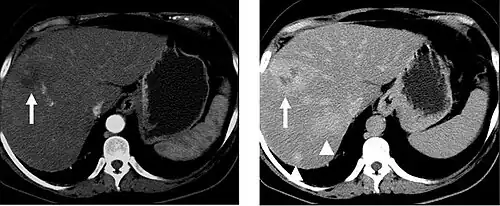

Liver masses

When evaluating hepatic masses, it can be advantageous to have both late arterial and portal venous phase images (biphasic imaging, figure 4) since some tumors enhance briskly during the arterial phase (hepatocellular carcinoma, hepatic adenoma, follicular nodular hyperplasia (FNH), and hypervascular metastasis), but may be occult or difficult to characterize on portal venous phase imaging alone (figure 6). However, it should be stressed that the addition of late arterial phase images is only indicated if one of these tumors is suspected, or if there is a need for further characterization of a hepatic mass, since the large majority of patients will not benefit from the addition of this phase. In addition, if there is a need to definitively characterize a hepatic mass, MRI is generally more sensitive and specific, with no associated radiation dose.

Transient hepatic attenuation differences in the arterial phase may mimic diseases of the liver.